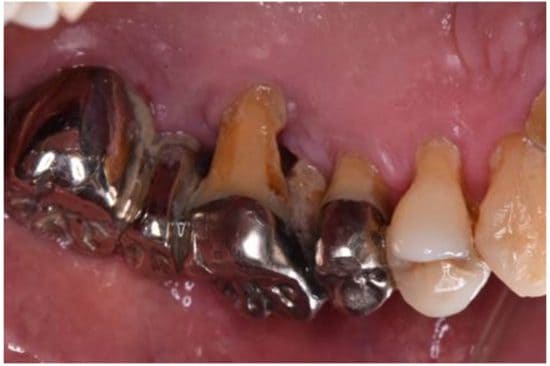

保険診療のクオリティは、やはり自費診療には敵わず、銀歯の下でむし歯が再発する「二次カリエス」のリスクや、見た目年齢への影響もあります。

海外では、保険診療という概念がないため、日本の銀歯は不思議がられることも多いです。時間コスト・再治療コスト・見た目の損失が大きいという難点があるのです。